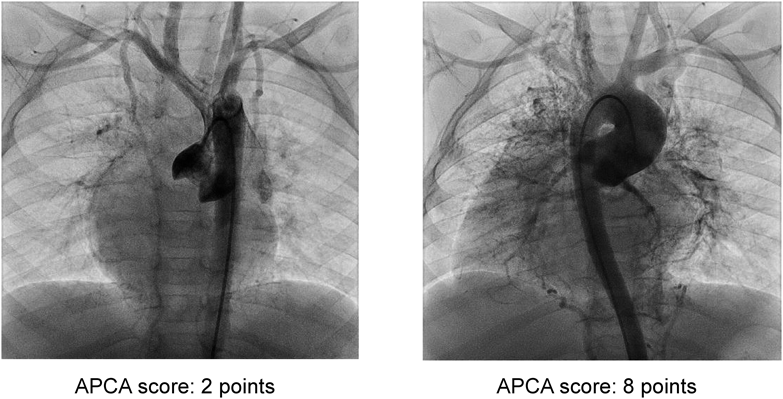

2009年1月から2015年12月までに当院でFontan型手術を行った連続163人を対象とした.APCAの発達の程度を,心臓カテーテル検査時の大動脈造影正面像の所見から,0点:APCA flowが認められない,1点:APCA flowが認められるが肺静脈はほとんど造影されない,2点:APCAから肺静脈がはっきりと造影される,の3段階に点数化し,左右内胸動脈領域,左右鎖骨下動脈領域,下行大動脈領域の計5か所のscoreの総和(最大10点,最少0点)を算出し,Fontan術前と術後6か月後の比較を全163例で,術後5年以上経過した後にカテーテル検査が行われていた35例ではFontan術前,術後6か月時との比較を行った.scoringの例をFig. 2に示す.大動脈造影は,大動脈弁直上に配置した4.2Fr. pigtailカテーテルから原則1 mL/kgの造影剤を1.5~2.0秒で注入し,フレームレート25fpsでAPCAの流入先が確認できるまで撮像した.また,Fontan術前後でMRIを施行した30例について,APCA flowの推移を定量的に観察した.APCA flowの算出は,SVC, IVC, Aorta, RPA/LPA, RPV/LPVの血流量を算出した後, (1) Q coll-syst = Q Aorta ( Q SVC + Q IVC ) および (2) Q coll-pulm =( Q RPV Q RPA )+( Q LPV Q LPA ) の式7, 8)を用いて行い,両者の平均値を採用した.

Fig. 2 Representative examples of APCA scoring

APCA=aorto-pulmonary arterial collateral arteries